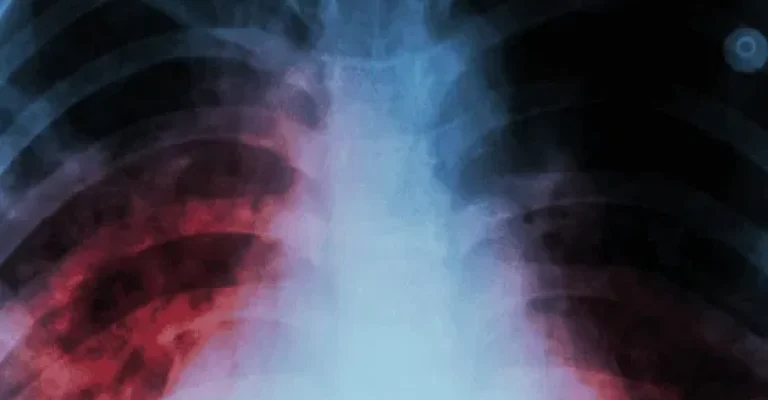

The lung has an extraordinary capacity for self-repair, but it is exposed to numerous damaging environmental and endogenous factors.

Stem cell therapy offers a groundbreaking approach to treating various lung diseases by promoting tissue repair, reducing inflammation, and modulating the immune response. Exosomes, small extracellular vesicles derived from stem cells, complement these effects by delivering growth factors, proteins, and genetic material directly to damaged tissues.